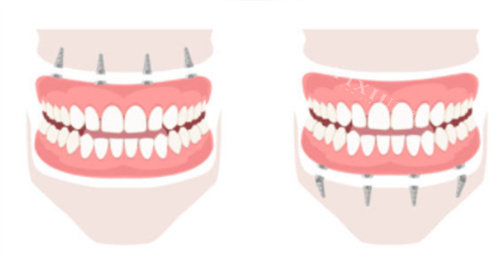

种植牙方面,每颗可享受1000元10000元专项消费券,半口/全口种植牙可享受10000元30000元专项消费券。

对于半口缺牙修复,贴补额度也有所提高,需要1999元,大大降低了半口缺牙患者的治疗费用。